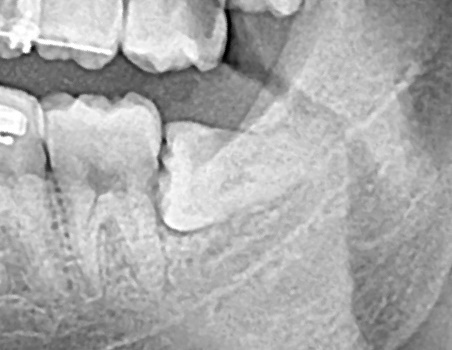

- Зуб 38 полностью в костной ткани.

- Коническая форма корня усложняет процесс экстракции.

- Наличие плотной костной ткани в углу нижней челюсти.

- Нижнечелюстной канал с 0,1мм от верхушки зуба.

- И для полной картины — разделение корня на 2 отдельно расположенных верхушки!

Я использовал все инструменты, тактики, фишки и тд!

Но этот зуб был уникальным — он сказал мне думай шире!

Мы это сделали а амбулаторных условиях.

Пациент доволен, осложнений нет, все отлично заживает!

Могу с полной уверенностью сказать, что это был самый сложный случай на моей практике!

Время операции 100 минут! Сложность 10/10!